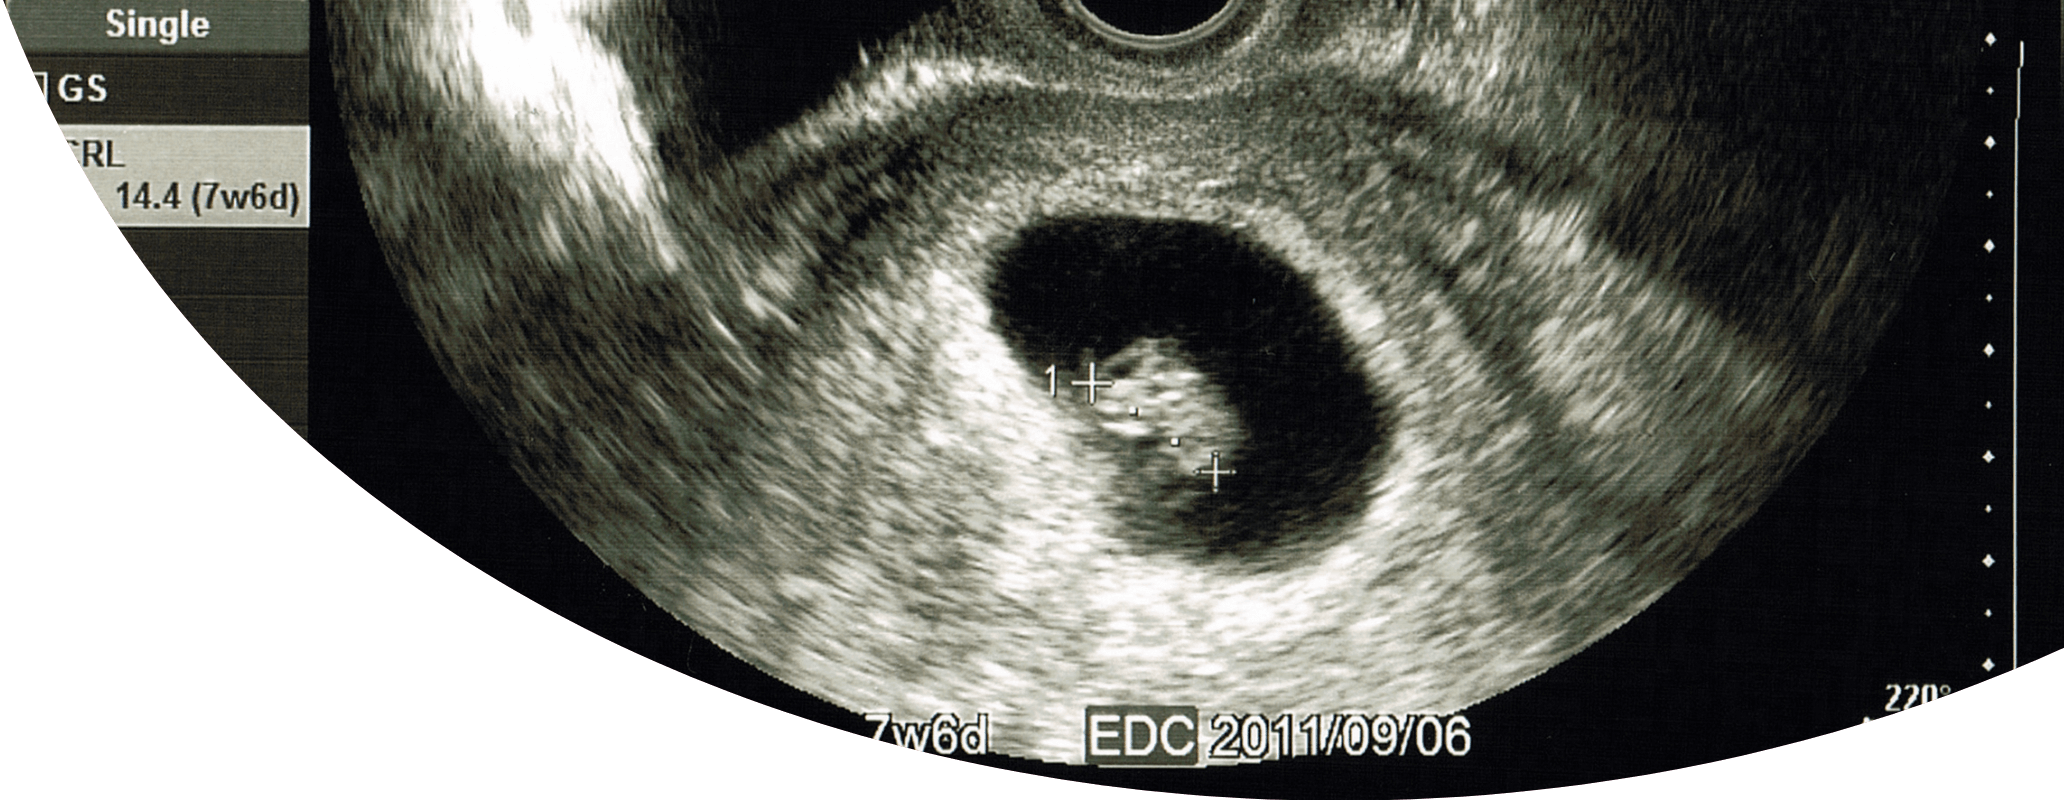

NIPTとは

NIPTは非侵襲性出生前遺伝学的検査とも呼ばれ、妊娠9〜10週以降に母親の血液を採取して行う検査となっています。

おなかの中で成⻑する赤ちゃんはお母さんと胎盤で血管を通してつながっていて、その血管から赤ちゃんに栄養が送られています。そのため、赤ちゃんのDNAの一部がこの血管を通じてお母さんの体内へ移動して、お母さんの血液中に少量存在するのです。これがお母さんの血液を検査することで赤ちゃんの情報がわかる理由です。

NIPTのメリットとしては、妊娠9〜10週という早期にできる検査であって胎児に影響を与えることなく検査ができる事が挙げられます。ただし、お母さんの血液を使用して検査するので確率は低いですが、お母さんのDNA情報を検査してしまう可能性があり、確定診断ではありません。

NIPTはあくまで赤ちゃんが染色体異常を持つ可能性の高さをみる検査に過ぎない事を念頭に入れておく必要があります。

NIPT検査では、赤ちゃんが、21トリソミー(ダウン症)や18トリソミー(エドワーズ症候群)、13トリソミー(パトー症候群)という染色体異常をもって産まれてくる可能性が分かります。妊婦が高齢であるほど赤ちゃんが染色体異常疾患をもって生まれてくる確率が高くなる事が知られており、NIPTはそのような病気を調べられる検査になっています。